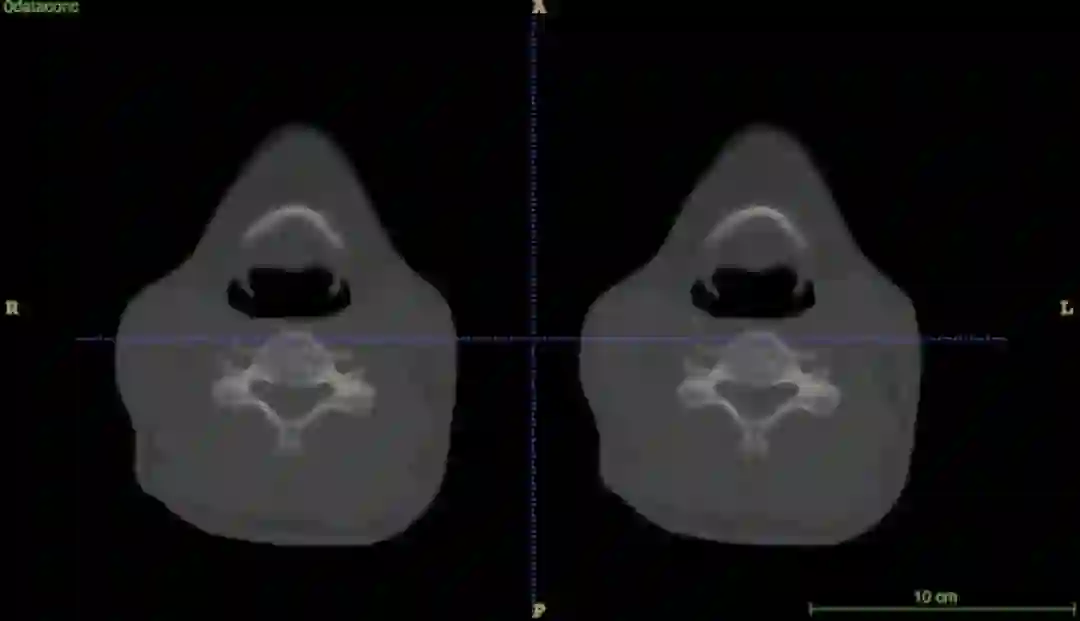

图1:器官神经网络危及器官分割结果

图 1 为器官神经网络危及器官分割结果,其中绿色为医生标注,红色为器官神经网络预测结果,黄色表示标注和预测重合,结果显示高度一致。

从图 2 的动态效果图上,可以更清晰地在三维 CT 所有切片上看到器官神经网络预测和医生标注的比较,其中左边显示的是医生标注,右边显示的是器官神经网络预测结果。